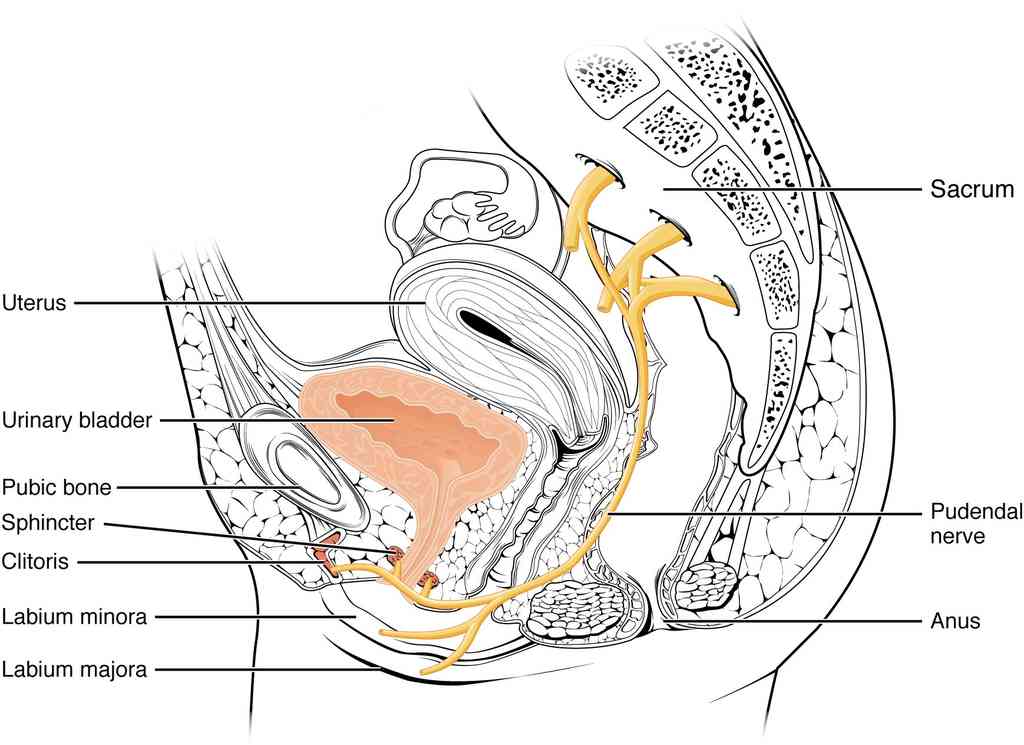

This page is under construction. For now, it is just a resource of the images found in the OpenStax Anatomy and Physiology Handbook. It wil slowly change into a revision tool. Each slide has a number. Use this to refer to the slide. When completed, it will have an unlabelled section, with labelled slides in parallel. On the unlabelled slides, write your answer and use the labelled slide to assess yourself. Keep track by also noting the number on each slide. Improvement at each attempt is important, more so than full marks on a first attempt.